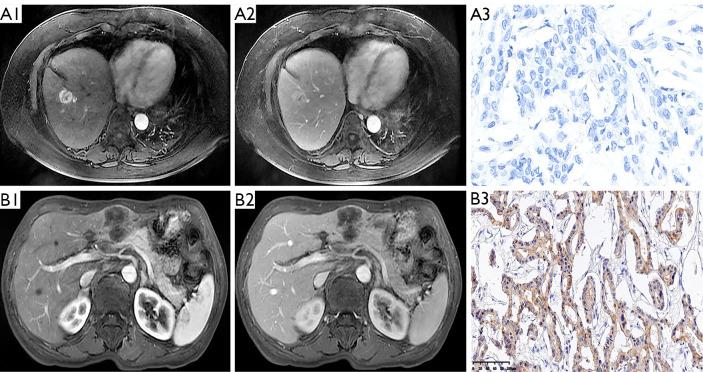

Prediction of PD-L1 expression and prognosis of mass-forming intrahepatic cholangiocarcinoma based on preoperative magnetic resonance imaging.

In clinical practice, only a subset of patients with tumor respond to immune checkpoint inhibitors. Therefore, the primary challenge lies in identifying the subgroup of candidates who will derive the greatest benefit from this type of therapy. Previous studies have indicated that the positive expression of programmed cell death ligand 1 (PD-L1) in tumors is associated with treatment response. In this study, we aimed to investigate the predictive value of preoperative magnetic resonance imaging (MRI) for PD-L1 expression and the prognosis of patients with mass-forming intrahepatic cholangiocarcinoma (MICC).

PD-L1 expression was significantly associated with enhancement patterns in the arterial phase of enhanced MR images [odds ratio (OR): 0.12; 95% confidence interval (CI): 0.04-0.37]. A predictive model for PD-L1 expression was established, with an AUC of 0.722 (95% CI: 0.632-0.811). Hepatic lobe atrophy [hazard ratio (HR): 2.036; 95% CI: 1.136-3.650], enhancement patterns (HR: 0.509; 95% CI: 0.295-0.877), lymph node metastasis (LNM) (HR: 1.715; 95% CI: 1.005-2.926), and carcinoembryonic antigen (CEA) (HR: 1.664; 95% CI: 1.007-2.750) were identified as prognostic factors for patients with MICC. The clinical OS model [concordance index (C-index): 0.875; 95% CI: 0.812-0.905] incorporating these independent predictors effectively stratified patients with MICC into high- and low-risk groups, with the 1-, 3-, and 5-year survival rates for the two groups being 56.5%, 17.4%, and 15.2%, respectively, and 89.1%, 58.7%, and 52.2%, respectively (P<0.001). Furthermore, the calibration curve of the clinical OS model demonstrated exceptional concordance between the predictions and actual observations.

Preoperative MRI may be a noninvasive means to predicting PD-L1 expression and prognosis in patients with MICC.